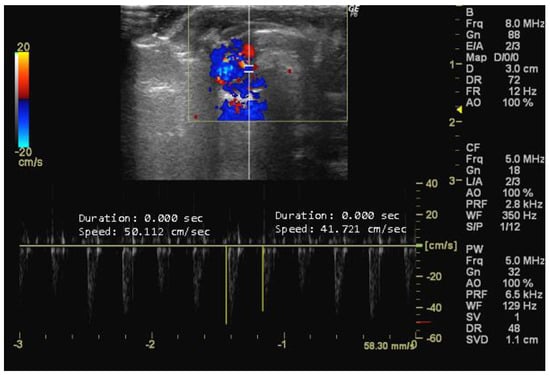

- How to measure E and A peaks

Apical Five-Chamber View

- How to measure LVET